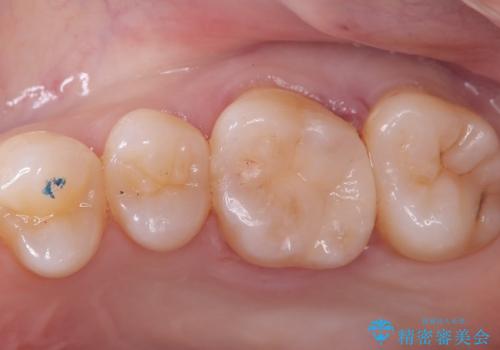

咬合面に穴が空き、歯の中でう蝕が広がっていました。この歯が過去に咬合面う蝕を経験しCR修復を受けていること、今回歯質とCRの境目からの二次う蝕になっていることを説明し、適合や材料安定性の良いセラミックインレーでのやり替えとなりました。

セット時はラバーダム防湿を行っています。